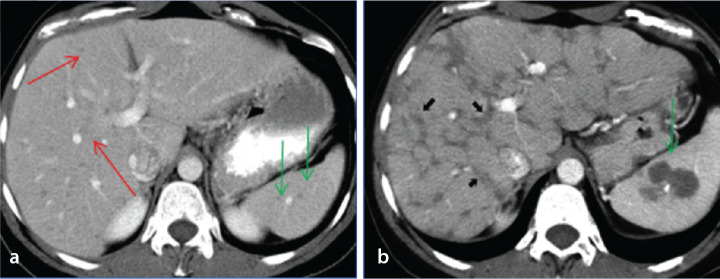

肝脏的非肿瘤样病变可能与肝肿瘤相似。在许多情况下,需要进行活组织检查以确认病理。不过,有几种肿瘤样病变可以得到正确诊断或前瞻性建议,从而使患者免于不必要的焦虑和花费。在这篇以图像为重点的综述中,我们介绍了八个此类实体的超声、计算机断层扫描、磁共振成像和正电子发射断层扫描特征。讨论了提示正确病理的线索,并描述了通常的临床环境。许多此类病变的治疗方法与真正的肿瘤不同,在介绍的许多病例中还讨论了当前的治疗方案。阅读完本文后,读者将对这些病变有更好的了解,并知道在哪些情况下应将其纳入鉴别诊断。

Non-neoplastic tumor-like conditions of the liver can appear similar to hepatic neoplasms. In many cases, a biopsy is required to confirm the pathology. However, several tumor-like conditions can be correctly diagnosed or suggested prospectively, thus saving patients from unnecessary anxiety and expense. In this image-focused review, we present the ultrasound, computed tomography, magnetic resonance imaging, and positron emission tomography scan features of eight such entities. Clues that indicate the correct pathology are discussed, and the usual clinical setting is described. Many of these lesions are treated differently from true neoplasms, and the current treatment plan is discussed in many of the cases presented. After reviewing this article, the reader will have a better understanding of these lesions and the situations in which they should be included in the differential diagnosis.